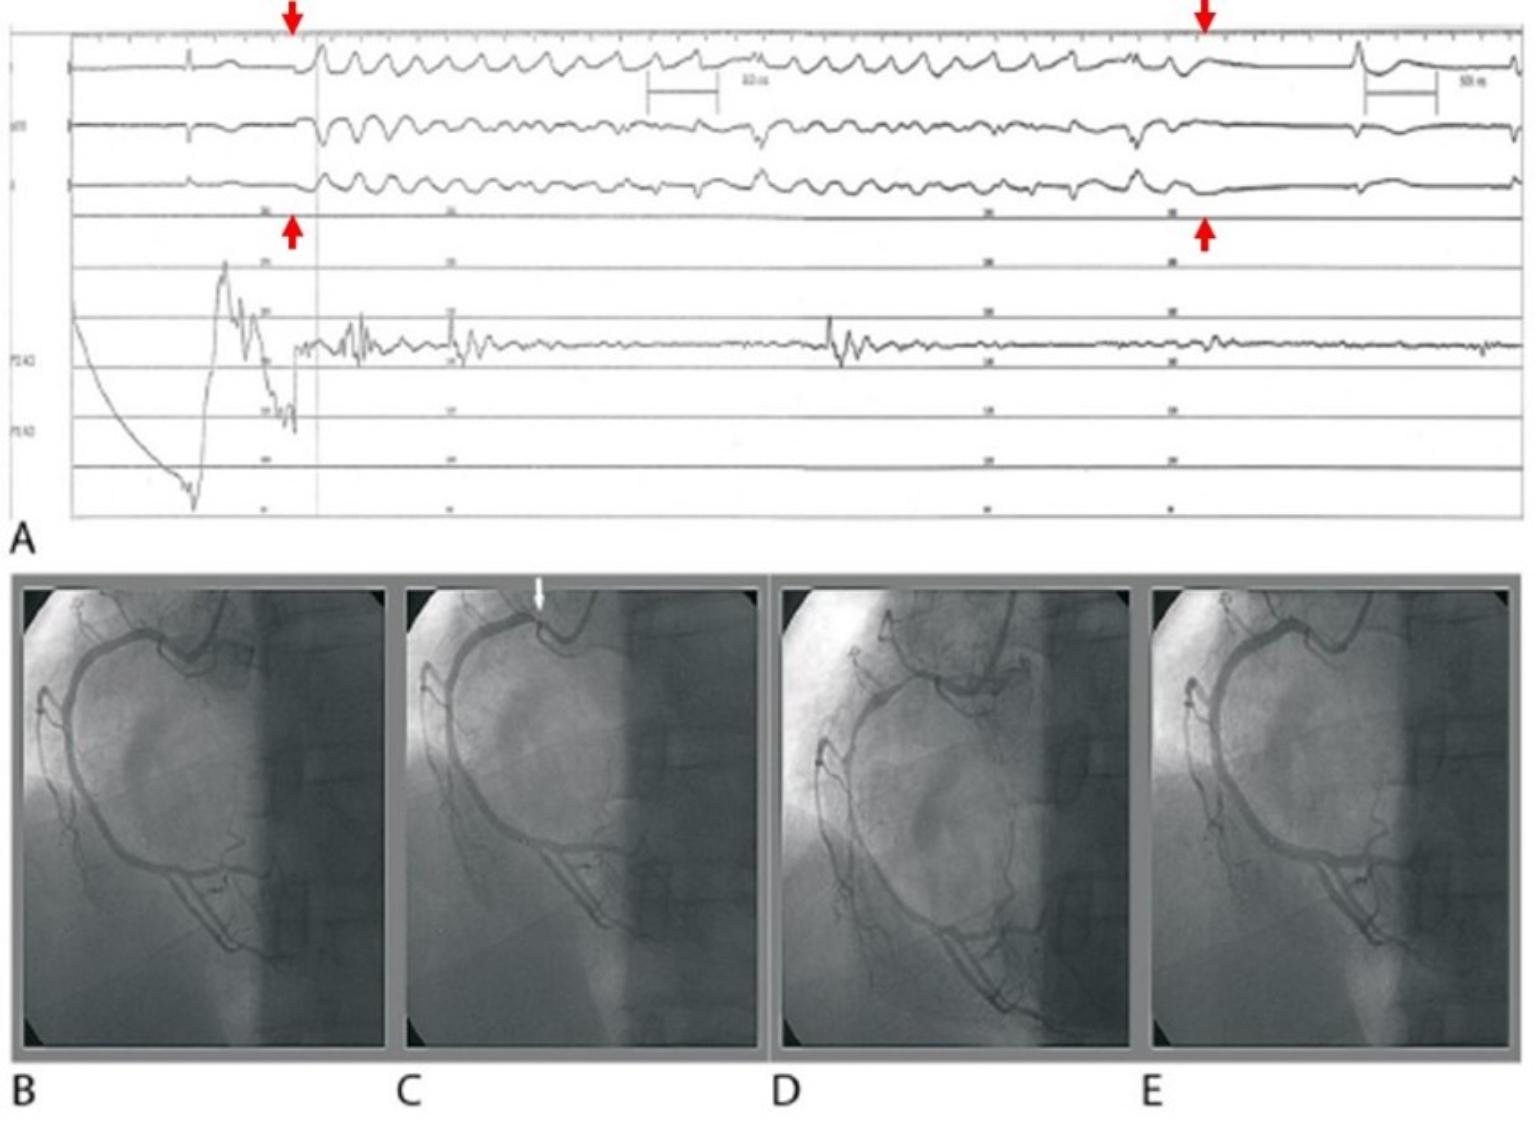

心導管心血管痙攣誘發檢查全球目前無死亡或嚴重副作用案例

心血管痙攣成因多變,且症狀不同於心血管阻塞。洪明佑表示,不論是心電圖、超音波還是電腦斷層都只能作為輔助,心導管心血管痙攣誘發檢查是心血管痙攣的唯一診斷方式,其概念類似心律不整電生理誘發檢查及暈厥傾斜床誘發檢查,根據1999年美國心臟學會臨床指引,這是敏感度高、特異性佳且安全的檢查。

但坊間時有誤解心血管痙攣誘發檢查屬於危險的檢查方式,甚至可能造成腦中風或心肌梗塞。對此,洪明佑指出,國際研究與臨床紀錄文獻皆顯示「心導管心血管痙攣誘發檢查」是非常準確且安全的檢查方式,檢查時以心導管直接投藥於冠狀動脈,大幅縮短藥劑抵達心臟的路徑,劑量僅需過去靜脈投藥檢查的10分之1,安全性高且全球無任何中風、心肌梗塞或死亡等嚴重副作用案例,唯一的副作用是心律不整,但都可自行或用藥治療恢復,鼓勵民眾應積極就醫,避免延誤治療、危害健康。